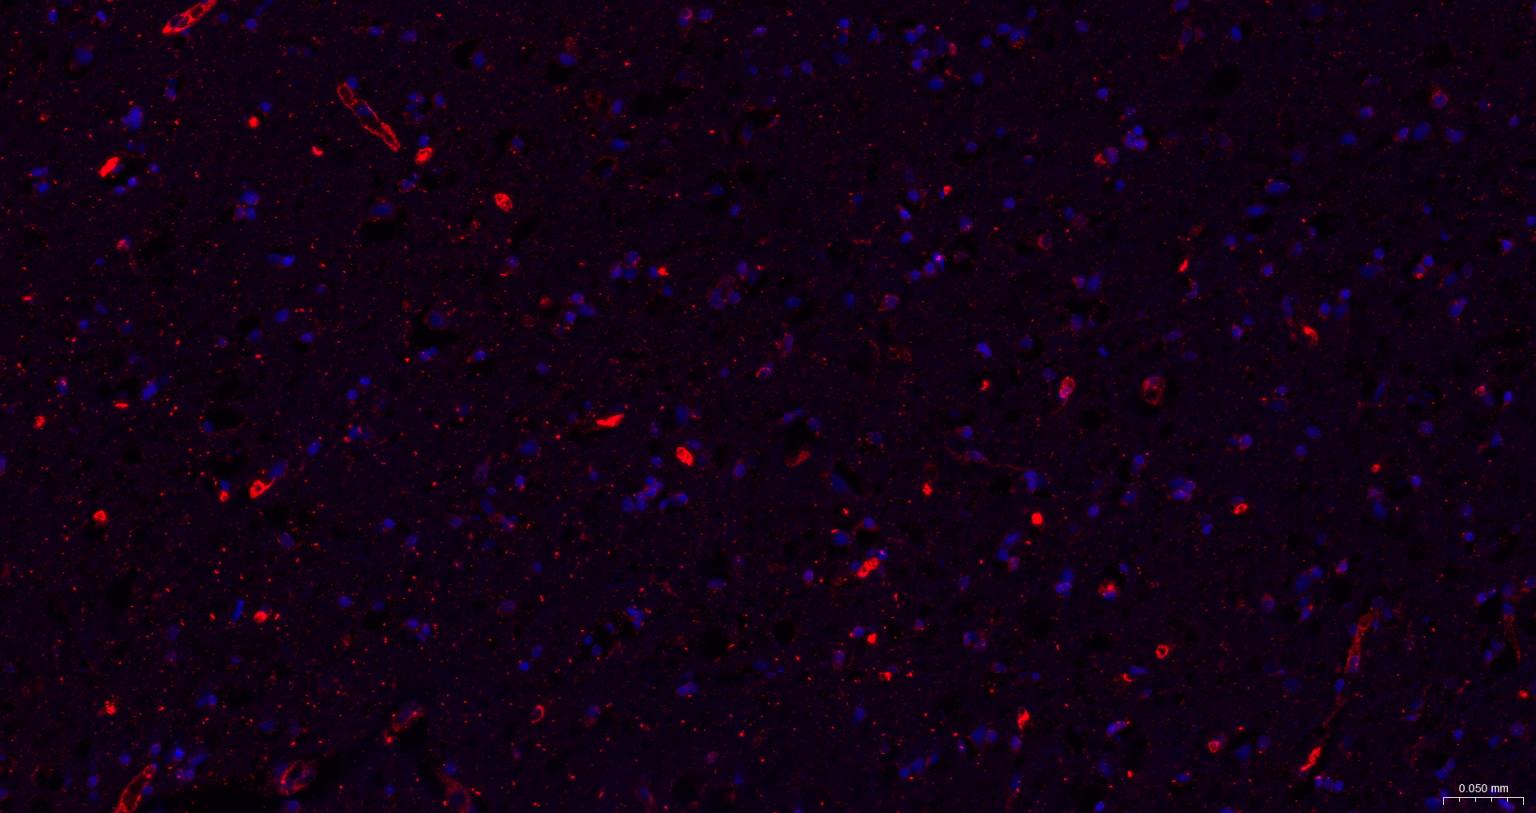

| IF | Human, Mouse, Rat | 1:100-500 |